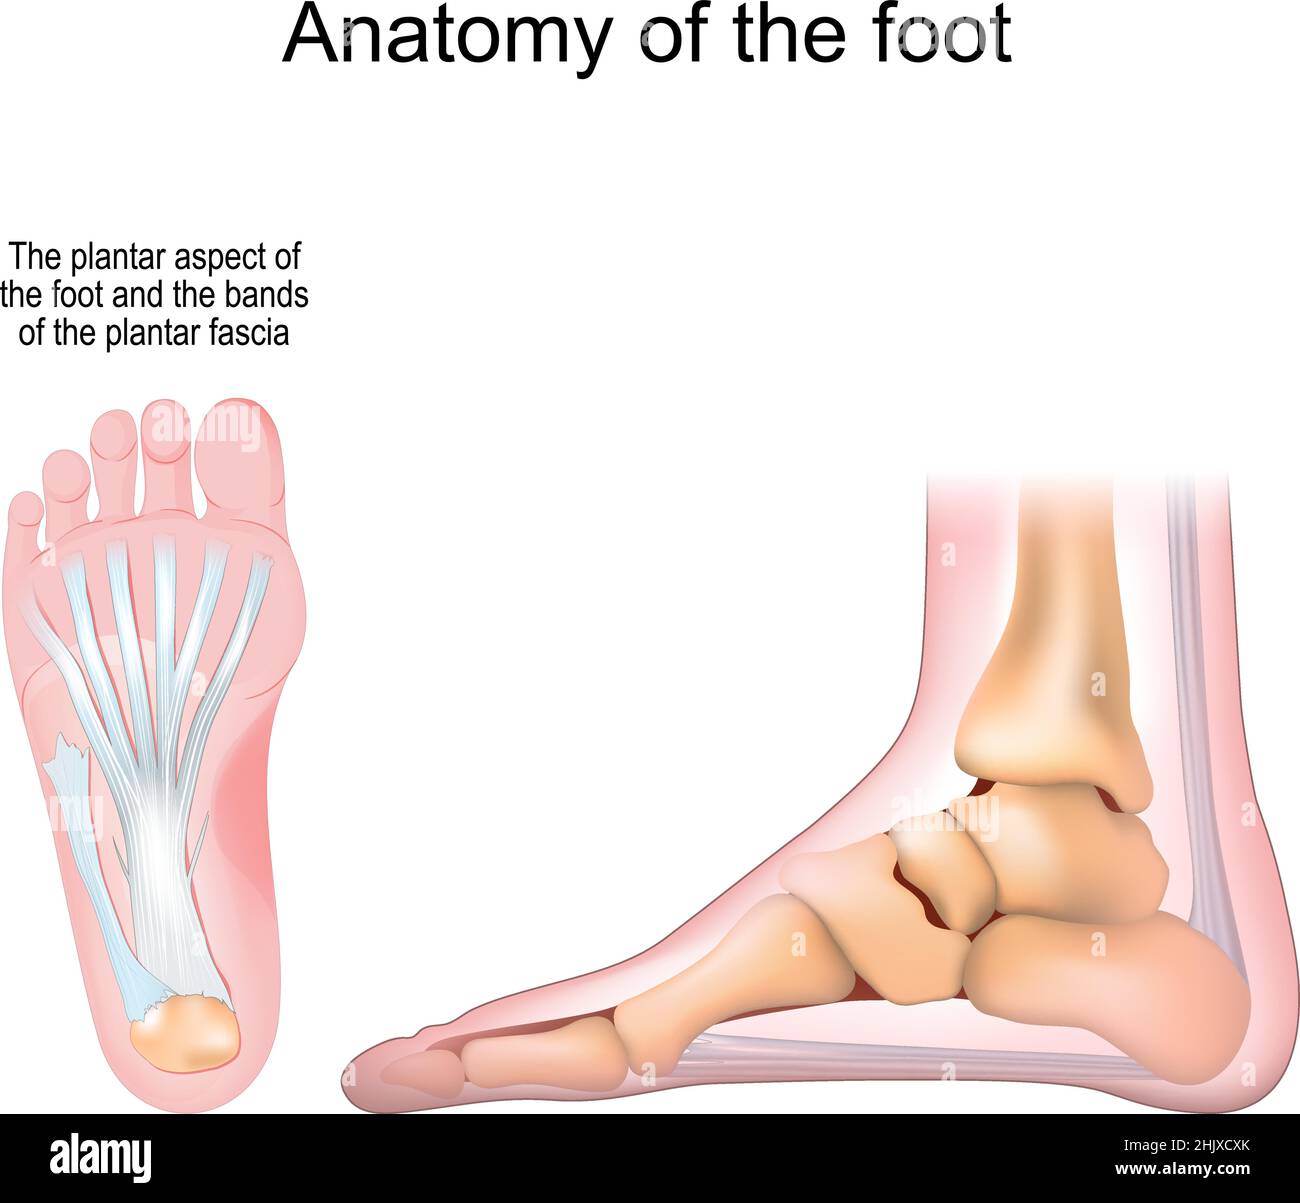

RF2J65WT4–Anatomie du pied. Pied humain avec le nom et la description de tous les os et sites. Vue de dessus et vue latérale. Arcs des pieds. Anatomie du squelette. Vecteur

RF2R3WKY1–Illustration médicale des principales parties des os du pied en vue latérale, avec annotations.

RF2X200ED–L'anatomie de l'articulation de la cheville. Région talocrurale ou os sauteur. Partie du corps humain où le pied et la jambe se rencontrent. Fascia plantaire et tendon d'Achille